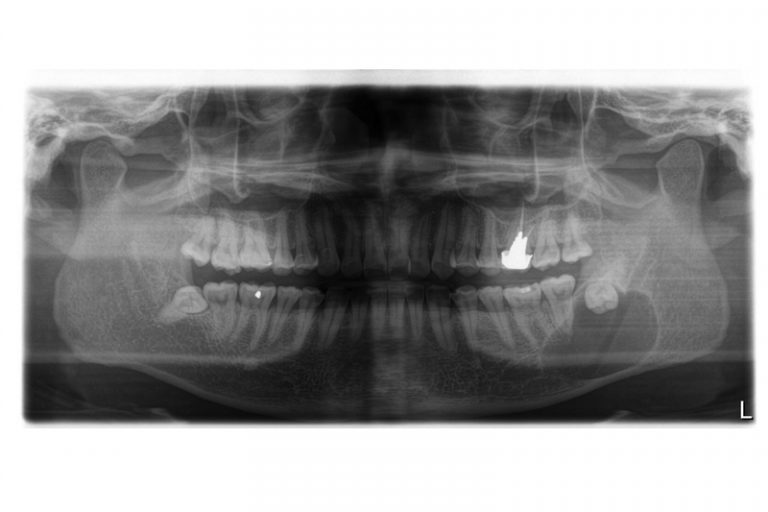

值得注意的是,智慧齒阻生或令組織病變而形成囊腫,因此別以為不痛不癢便無須理會智慧齒。

智慧齒阻生令顎骨內其他組織病變而形成顎骨囊腫